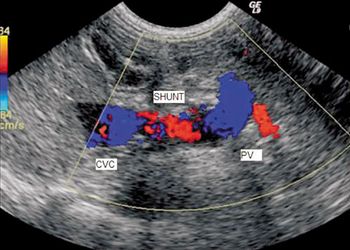

Pick the right diagnostic step in this senior dog.

When you have a patient with a hepatic vascular abnormality, how do you confirm it?

Add a little contrast to help you find your diagnosis.

Examine the imaging results to help solve this pug's problem.